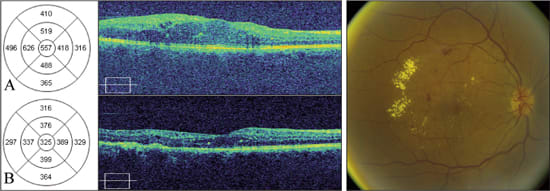

A 46-year-old female with a history of non-insulin dependent diabetes mellitus for 19 years was referred for evaluation of diabetic macular edema in both eyes. She had no other prior medical history. Best corrected visual acuity was 20/30 in the right eye, and SD-OCT demonstrated clinically significant macular edema with a central foveal thickness of 557 microns (Figure 2A).

Figure 2. Sequential SD-OCT images from a 46-year-old female with diabetic macular edema in the right eye. Color fundus photograph demonstrates hard exudates with associated macular edema.

A: Horizontal scans through the fovea show distortion of the normal foveal contour with central macular thickening. The retinal map shows a central foveal thickness of 557 μm. Best-corrected visual acuity was 20/30.

B: Two months after grid laser photocoagulation, SD-OCT reveals marked improvement of foveal thickness (325 μm) and restoration of the foveal contour. Best-corrected visual acuity was 20/20.

The patient was treated with grid laser photocoagulation in the right eye. At two months follow up, the visual acuity was 20/20. SD-OCT mirrored the clinical finding of improved macular edema, with a central foveal thickness of 325 microns (Figure 2B). At six months follow-up, visual acuity remained 20/20 with stable SD-OCT findings.